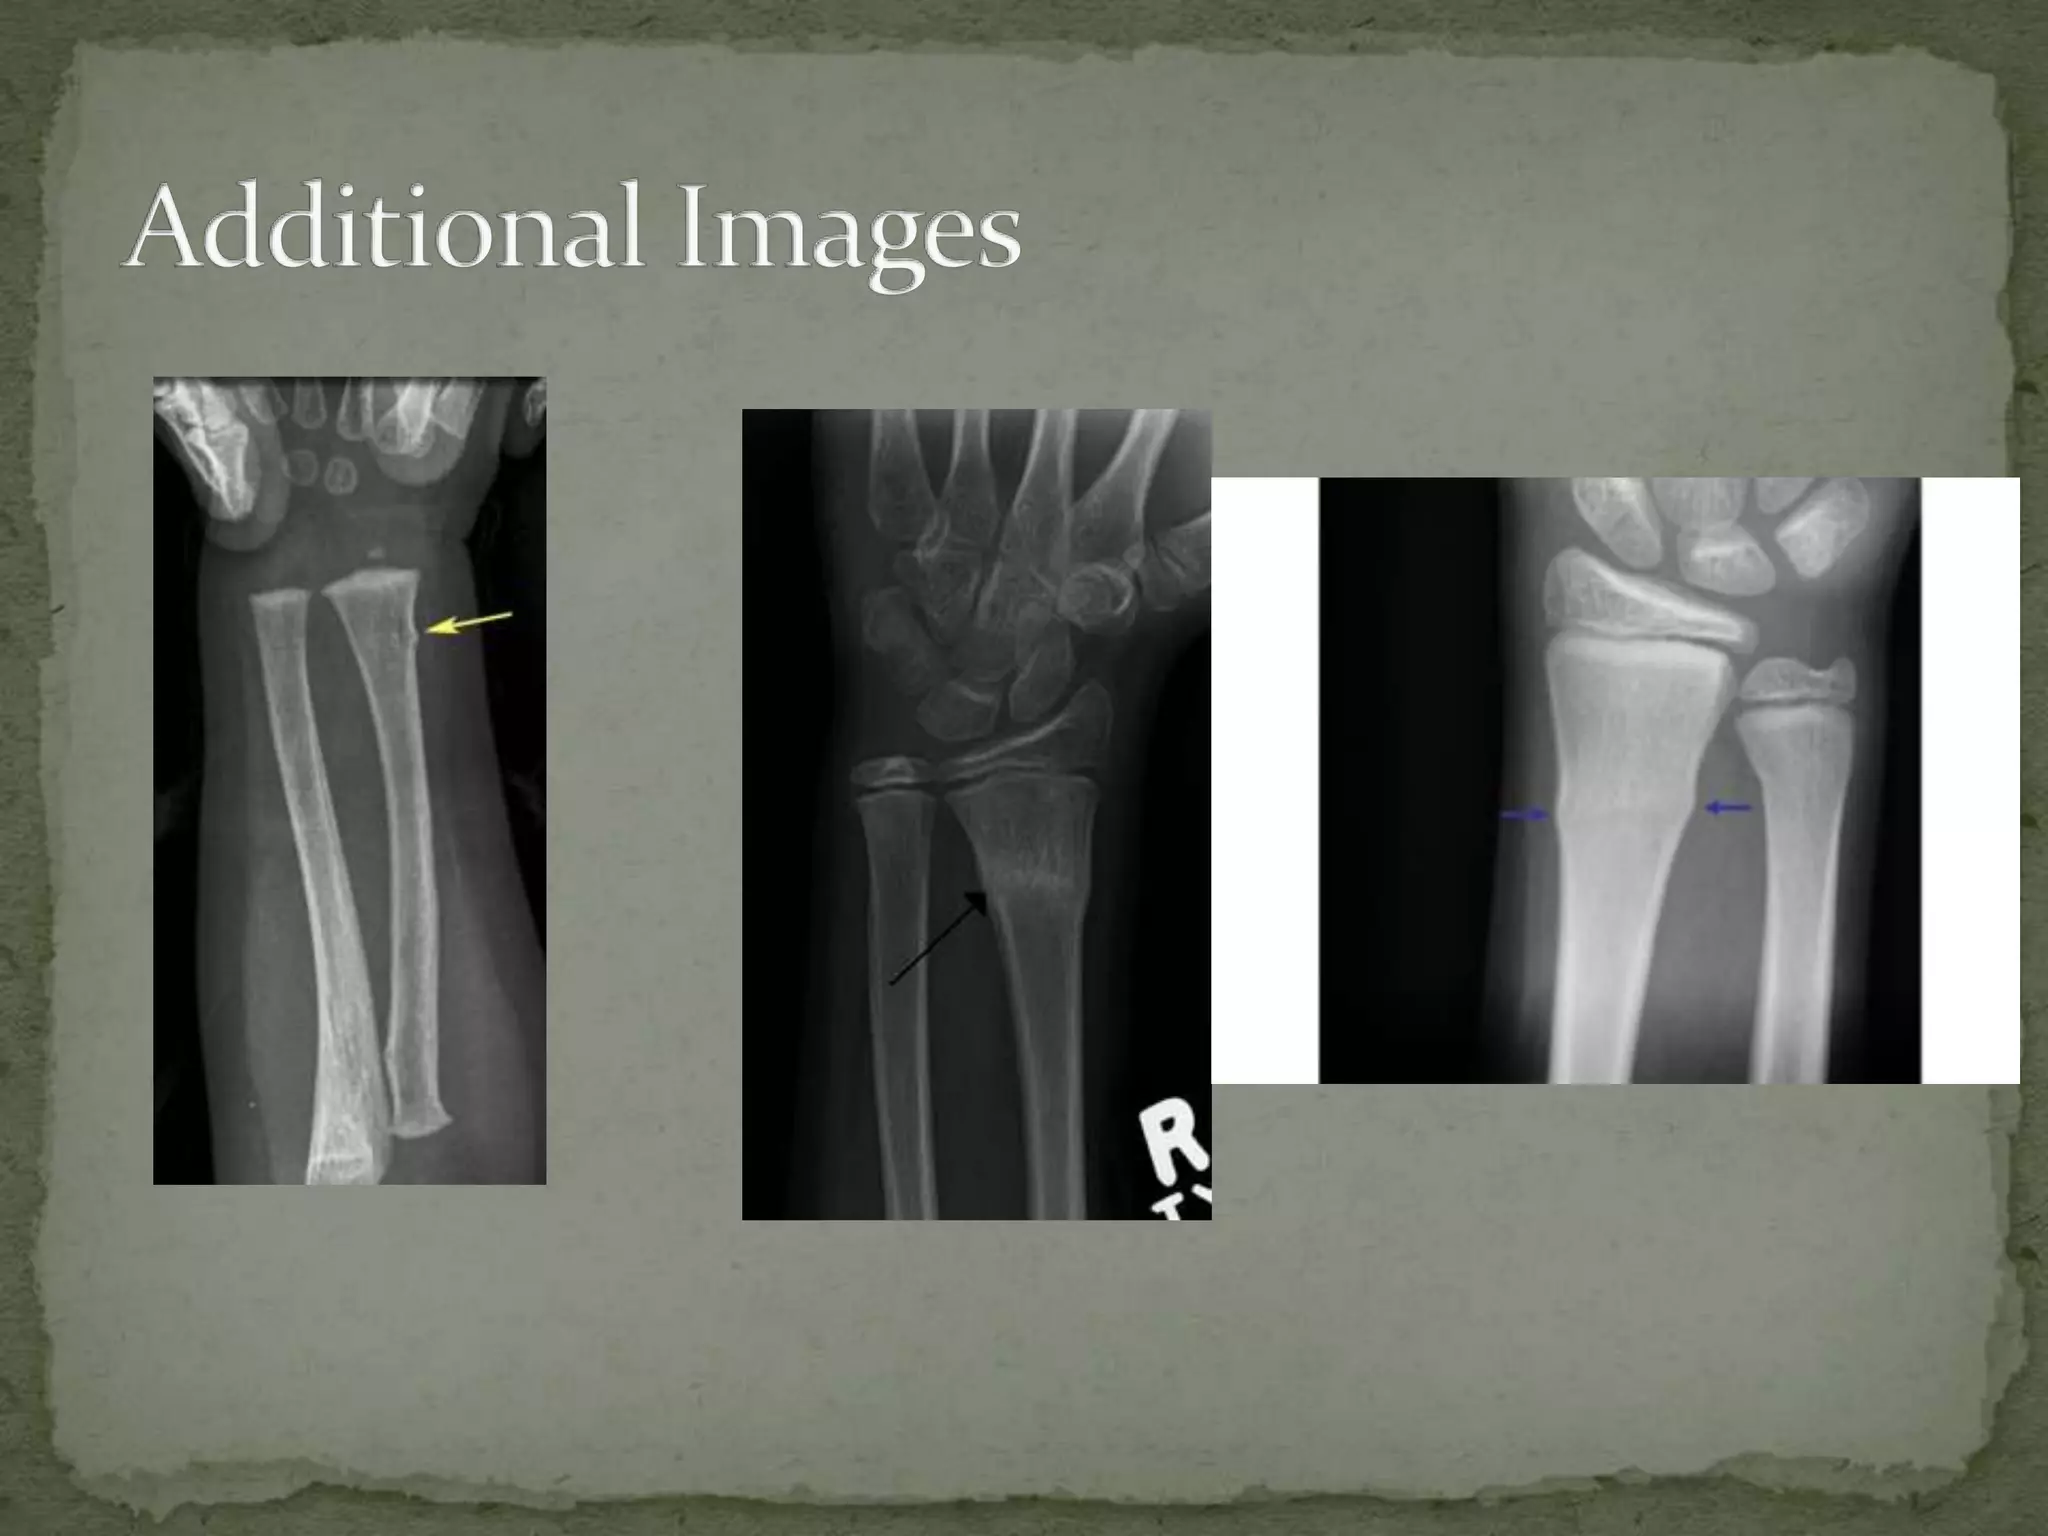

Torus fracture radius

Torus Fracture-Radius - Sumer's Radiology Blog

Torus Fracture-Radius - Sumer's Radiology Blog sumerdoc.blogspot.com

torus fracture radius radiology bone